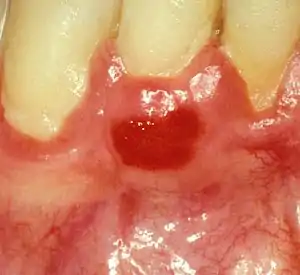

Plasma cell gingivitis appears as mild gingival enlargement and may extend from the free marginal gingiva on to the attached gingiva.[6] Sometimes it is blended with a marginal, plaque induced gingivitis, or it does not involve the free marginal gingiva. It may also be found as a solitude red area within the attached gingiva (pictures). In some cases the healing of a plaque-induced gingivitis or a periodontitis resolves a plasma cell gingivitis situated a few mm from the earlier plaque-infected marginal gingiva. In case of one or few solitary areas of plasma cell gingivitis, no symptoms are reported from the patient. Most often solitary entities are therefore found by the dentist.[2]

The gums are red, friable, or sometimes granular, and sometimes bleed easily if traumatised.[6] The normal stippling is lost.[7] There is not usually any loss of periodontal attachment.[6] In a few cases a sore mouth can develop, and if so pain is sometimes made worse by toothpastes, or hot or spicy food.[7] The lesions can extend to involve the palate.[7]